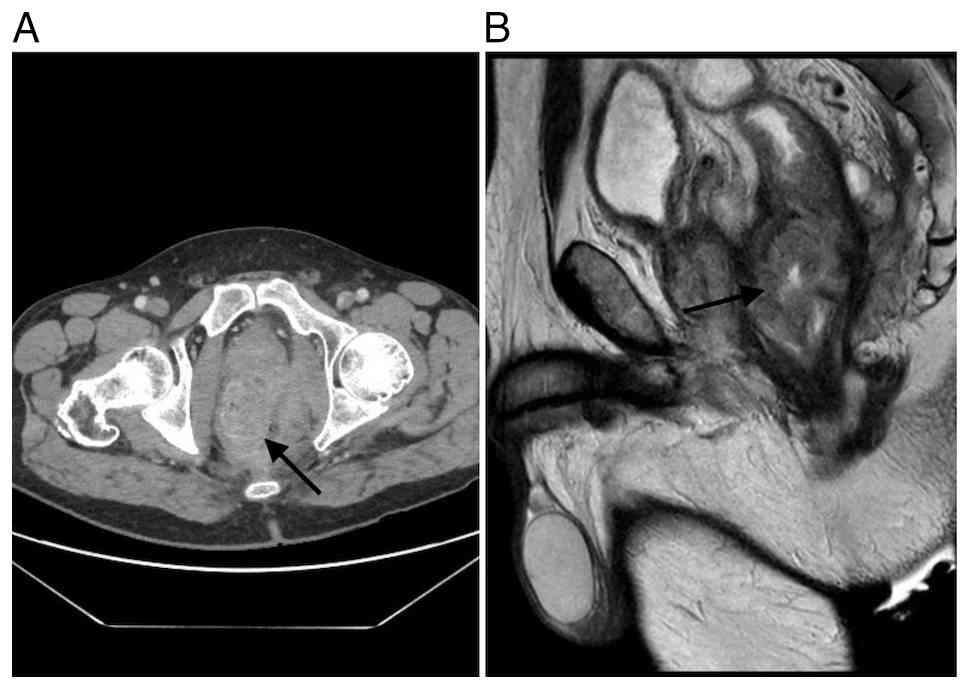

Postoperative computed tomography (CT) (Fig. 2) revealed an 8×6.7×8 cm presacral mass extending into the left ischiorectal fossa and infiltrating the gluteus maximus muscle. The mass was inseparable from the anorectal junction, puborectalis muscle, internal obturator muscle, seminal vesicles, and prostate, although no distant metastases were identified.

(A) CT scan and (B) MRI findings

before radiotherapy treatment (the arrow indicates the tumoral

mass).

Figure 2.

(A) CT scan and (B) MRI findings before radiotherapy treatment (the arrow indicates the tumoral mass).

Magnetic resonance imaging (MRI) (Fig. 2) confirmed a large tumor in the mid and lower rectum (81×75×84 mm, APxTRxCC), with extension through the muscularis propria into the left levator ani muscle, ischioanal space, and subcutaneous gluteal tissues. There was contact with the left seminal vesicle and peripheral prostate, without clear invasion. Two pathologic lymph nodes were noted. The tumor was staged as T4bN1.